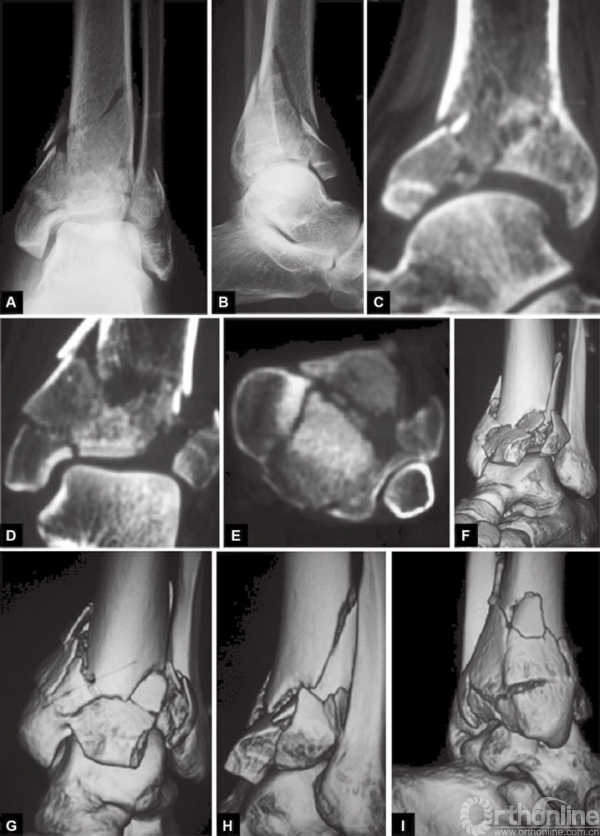

胫骨远端和踝关节的CT扫描和三维重建几乎是强制性的,它能产生一个更加直观的骨折模型,更好理解骨折块粉碎、位移和关节碎片的嵌入情况(图37.1、37.2)。这对手术的准备是极具价值的,比如帮助决定入路,骨折的复位以及钢针和螺钉的方向。对于多发伤患者,应进行全身的扫描。当怀疑有血管损伤是进行血管造影。

图2 A~I Pilon骨折C型,标准正位与侧位X线摄影。冠状位CT平扫和3D重建。好的成像有利于入路决定和手术的准备